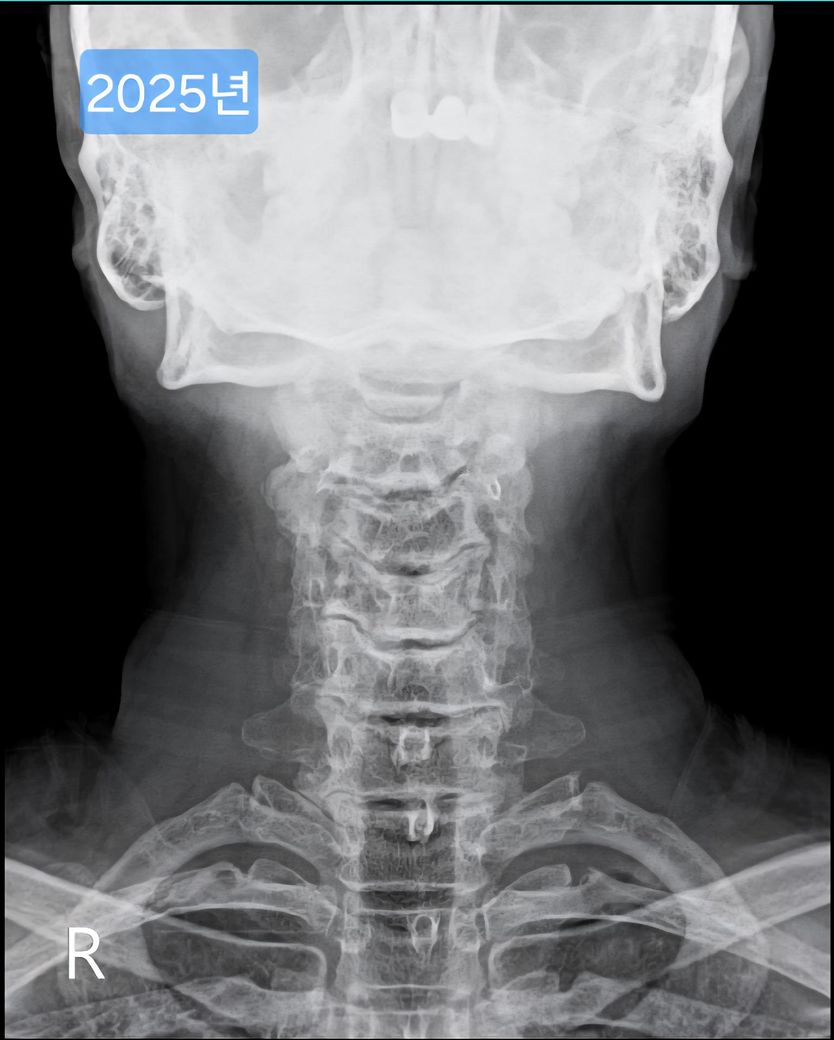

목이 일자목, 경추사이 공간 좁음 등 형태가 안 좋은데요.

여러 방도로 제 목 엑스레이 사진을 보여드리면

현재 목의 형태가 안 좋은건 충분히 알겠는데.

• 1번 째 사진

• 2번 째 사진

• 3번 째 사진

• 4번 째 사진